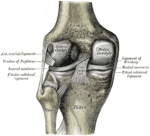

الركبة Knee مفصل تلتقي عنده عظمة الفخذ مع العظمة الكبيرة للساق السفلى. وتتحرك الركبة، مثل المفصّلة، ويمكنها أن تدور وتتحرك قليلاً من جهة إلى أخرى. والركبة أكثر قابلية للتلف من معظم المفاصل، إذ إنّها عُرضة لضغوط كبيرة عند النشاط الزائد. ومعظم إصابات الركبة التي تحدث في كرة القدم والرياضات الأخرى تنتج من التواء المفصل.

والرضفة (غطاء الركبة) عظمة مسطحة مثلثة صغيرة في مقدمة المفصل. وهي ليست موصولة بطريقة مباشرة مع أية عظمة أخرى. وتعمل أربطة عظمية على بقائها في مكانها.

وتتصل عظمة الفخذ والظنبوب (عظمة الساق السفلى الكبيرة) بثلاث طرق هي : 1 – بالأربطة (أنسجة قوية شبيهة بالوتر)، 2 – بالعضلات، 3 - بمحفظة زليلية. وتحيط المحفظة الزليلية بالمفصل. وأربطة الركبة هي الموصلات الأقوى بين عظمة الفخذ والظنبوب. وهذه الأربطة تمنع العظمات من التزحزح عن مكانها.